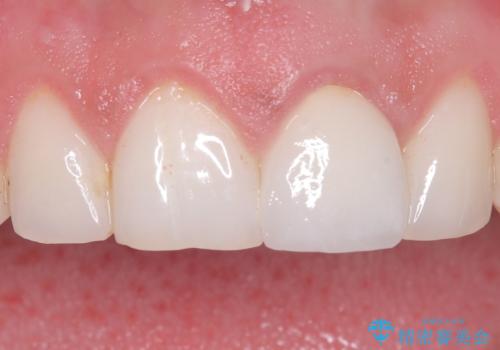

[ セラミック治療 ] 前歯の見た目を改善したい

![[ セラミック治療 ] 前歯の見た目を改善したいの症例 治療前](https://seimitsushinbi.jp/wp/wp-content/uploads/2025/10/IMG_9990-2-500x350.jpg?v=1761816440)

![[ セラミック治療 ] 前歯の見た目を改善したいの症例 治療後](https://seimitsushinbi.jp/wp/wp-content/uploads/2025/10/IMG_9934-500x350.jpg?v=1761816431)